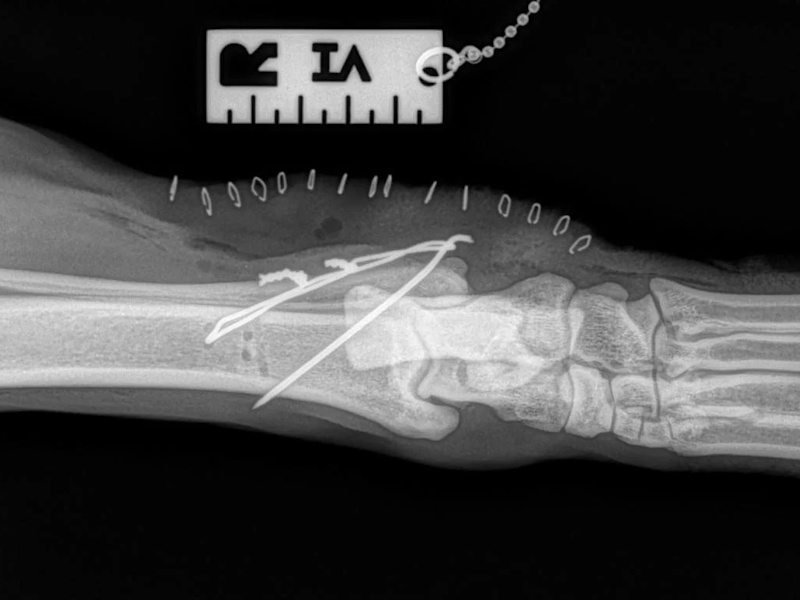

Fore Limb (Humerus, Radius/Ulnar, Metacarpus)